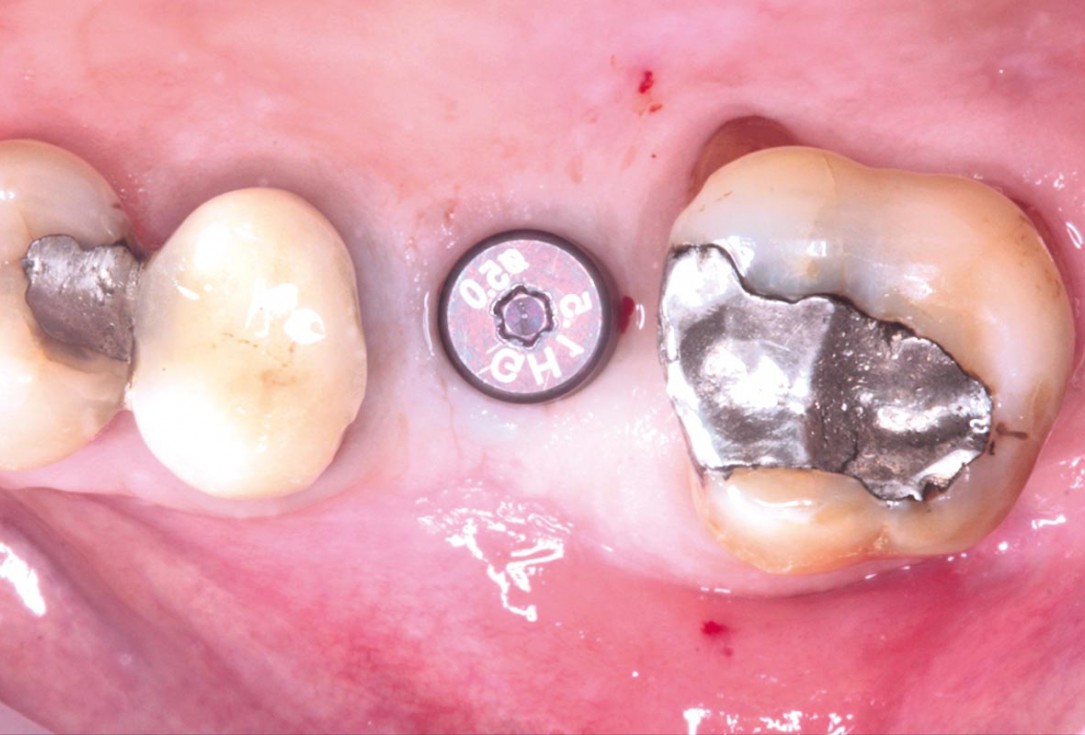

28/35 - Application of the healing cap after the second stageMaxillary sinus cyst removal using the Crocodile Technique and subsequent lateral sinus lift - Dres. C. Scognamiglio and A. Perucchi

29/35 - X-ray control after the second stageMaxillary sinus cyst removal using the Crocodile Technique and subsequent lateral sinus lift - Dres. C. Scognamiglio and A. Perucchi

30/35 - Peri-implant tissues at 3 weeks from the second stageMaxillary sinus cyst removal using the Crocodile Technique and subsequent lateral sinus lift - Dres. C. Scognamiglio and A. Perucchi

31/35 - Peri-implant tissues at 3 weeks from the second stageMaxillary sinus cyst removal using the Crocodile Technique and subsequent lateral sinus lift - Dres. C. Scognamiglio and A. Perucchi